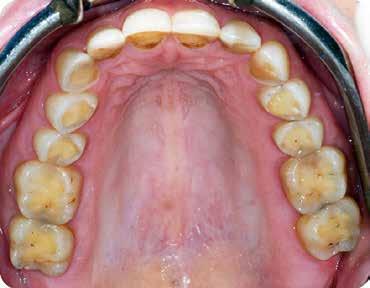

Anyagok és módszerek: 42 éves nő fordult a szerző rendelőjébe tüneti apikális parodontitisszel. A PA röntgenfelvételen az apex körül sugárzástól átlátszó kép és extrudált gyökércsatorna obturációs anyag volt látható, a CBCT-n megőrzött vestibuláris csont mellett (1–2. ábra). Mivel az elmúlt három évben kétszer

Szépen beállított ideiglenes korona volt jelen, kóros szondázási mélység és szondázási vérzés nélkül. Nem volt jelen sinus tractus (3–5. ábra). Tüneti apikális parodontitis 1. osztály (Von Arx&Cochrane 2001); B osztály (Kim&Kratchman 2005) és korábban elvégzett gyökérkezelés volt a végső diagnózis.